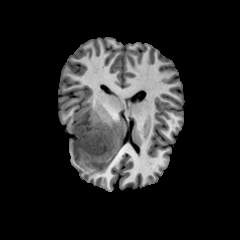

Figure 1: Example of moving (top) and fixed (bottom) image pairs. From left to right: brain MRI (T2w, T1w, T1Gd), abdomen CT from different subjects, retinal OCTA choroid, and retinal OCTA SCP scans

To address this problem, we propose a meta-learning-based registration meth-od that can efficiently use data from different domains. Specifically, we integrate an unsupervised learning-based registration model in a gradient-based meta-learning framework. The registration model is first trained using multiple registration datasets and then performs task-level learning using the multi-task data. The meta-learner finds an initialization point which can quickly adapt to various registration problems. After that, fine tuning is performed with the data of the target domain and applied to the test set. To demonstrate superiority, we trained the model for various 2D registration tasks from retinal Optical Coherence Tomography Angiography (OCTA) choroid, abdomen CT, and brain MRI scans and tested it on a registration of retinal OCTA Superficial Capillary Plexus (SCP) scans as shown in Fig. 1.

In our experiment, we used four datasets including retinal OCTA SCP, retinal OCTA choroid, abdomen CT, and Brain MRI. Both OCTA SCP and choroid datasets contained 368 moving and fixed image pairs collected from local university hospital, some of which were taken from same subjects at different times. The abdomen CT and brain MRI images were obtained from public Decathlon dataset [15]. Here, we define three tasks according to modality (T1w, T1Gd, and T2w) from the brain MRI dataset and two tasks in the abdomen CT dataset. Each 3D volume was divided in multiple axial slices and adjacent two slices were defined as a (M,F)𝑀𝐹(M,F) pair. All images were resized to a size of 400×400400400400\times 400 and histogram equalization was applied. Also, the range of intensity was rescaled to [0,1]. For training, we defined a set of five tasks as the source task set Tsource=subscript𝑇𝑠𝑜𝑢𝑟𝑐𝑒absentT_{source}= TbrainT1subscript𝑇𝑏𝑟𝑎𝑖𝑛𝑇1T_{brainT1}, TbrainT1Gdsubscript𝑇𝑏𝑟𝑎𝑖𝑛𝑇1𝐺𝑑T_{brainT1Gd}, TbrainT2subscript𝑇𝑏𝑟𝑎𝑖𝑛𝑇2T_{brainT2}, Tabdomensubscript𝑇𝑎𝑏𝑑𝑜𝑚𝑒𝑛T_{abdomen}, TChoroidsubscript𝑇𝐶𝑜𝑟𝑜𝑖𝑑T_{Choroid}. For evaluation, retinal OCTA SCP dataset was used as target domain data Dtargetsubscript𝐷𝑡𝑎𝑟𝑔𝑒𝑡D_{target}. It was divided into a fine-tuning set Tfinetunesubscript𝑇𝑓𝑖𝑛𝑒𝑡𝑢𝑛𝑒T_{fine-tune} (294 pairs) and a test set Ttestsubscript𝑇𝑡𝑒𝑠𝑡T_{test} (74 pairs). For evaluation, we manually labeled 20similar-to\sim30 bifurcation points on image pairs in Ttestsubscript𝑇𝑡𝑒𝑠𝑡T_{test}.